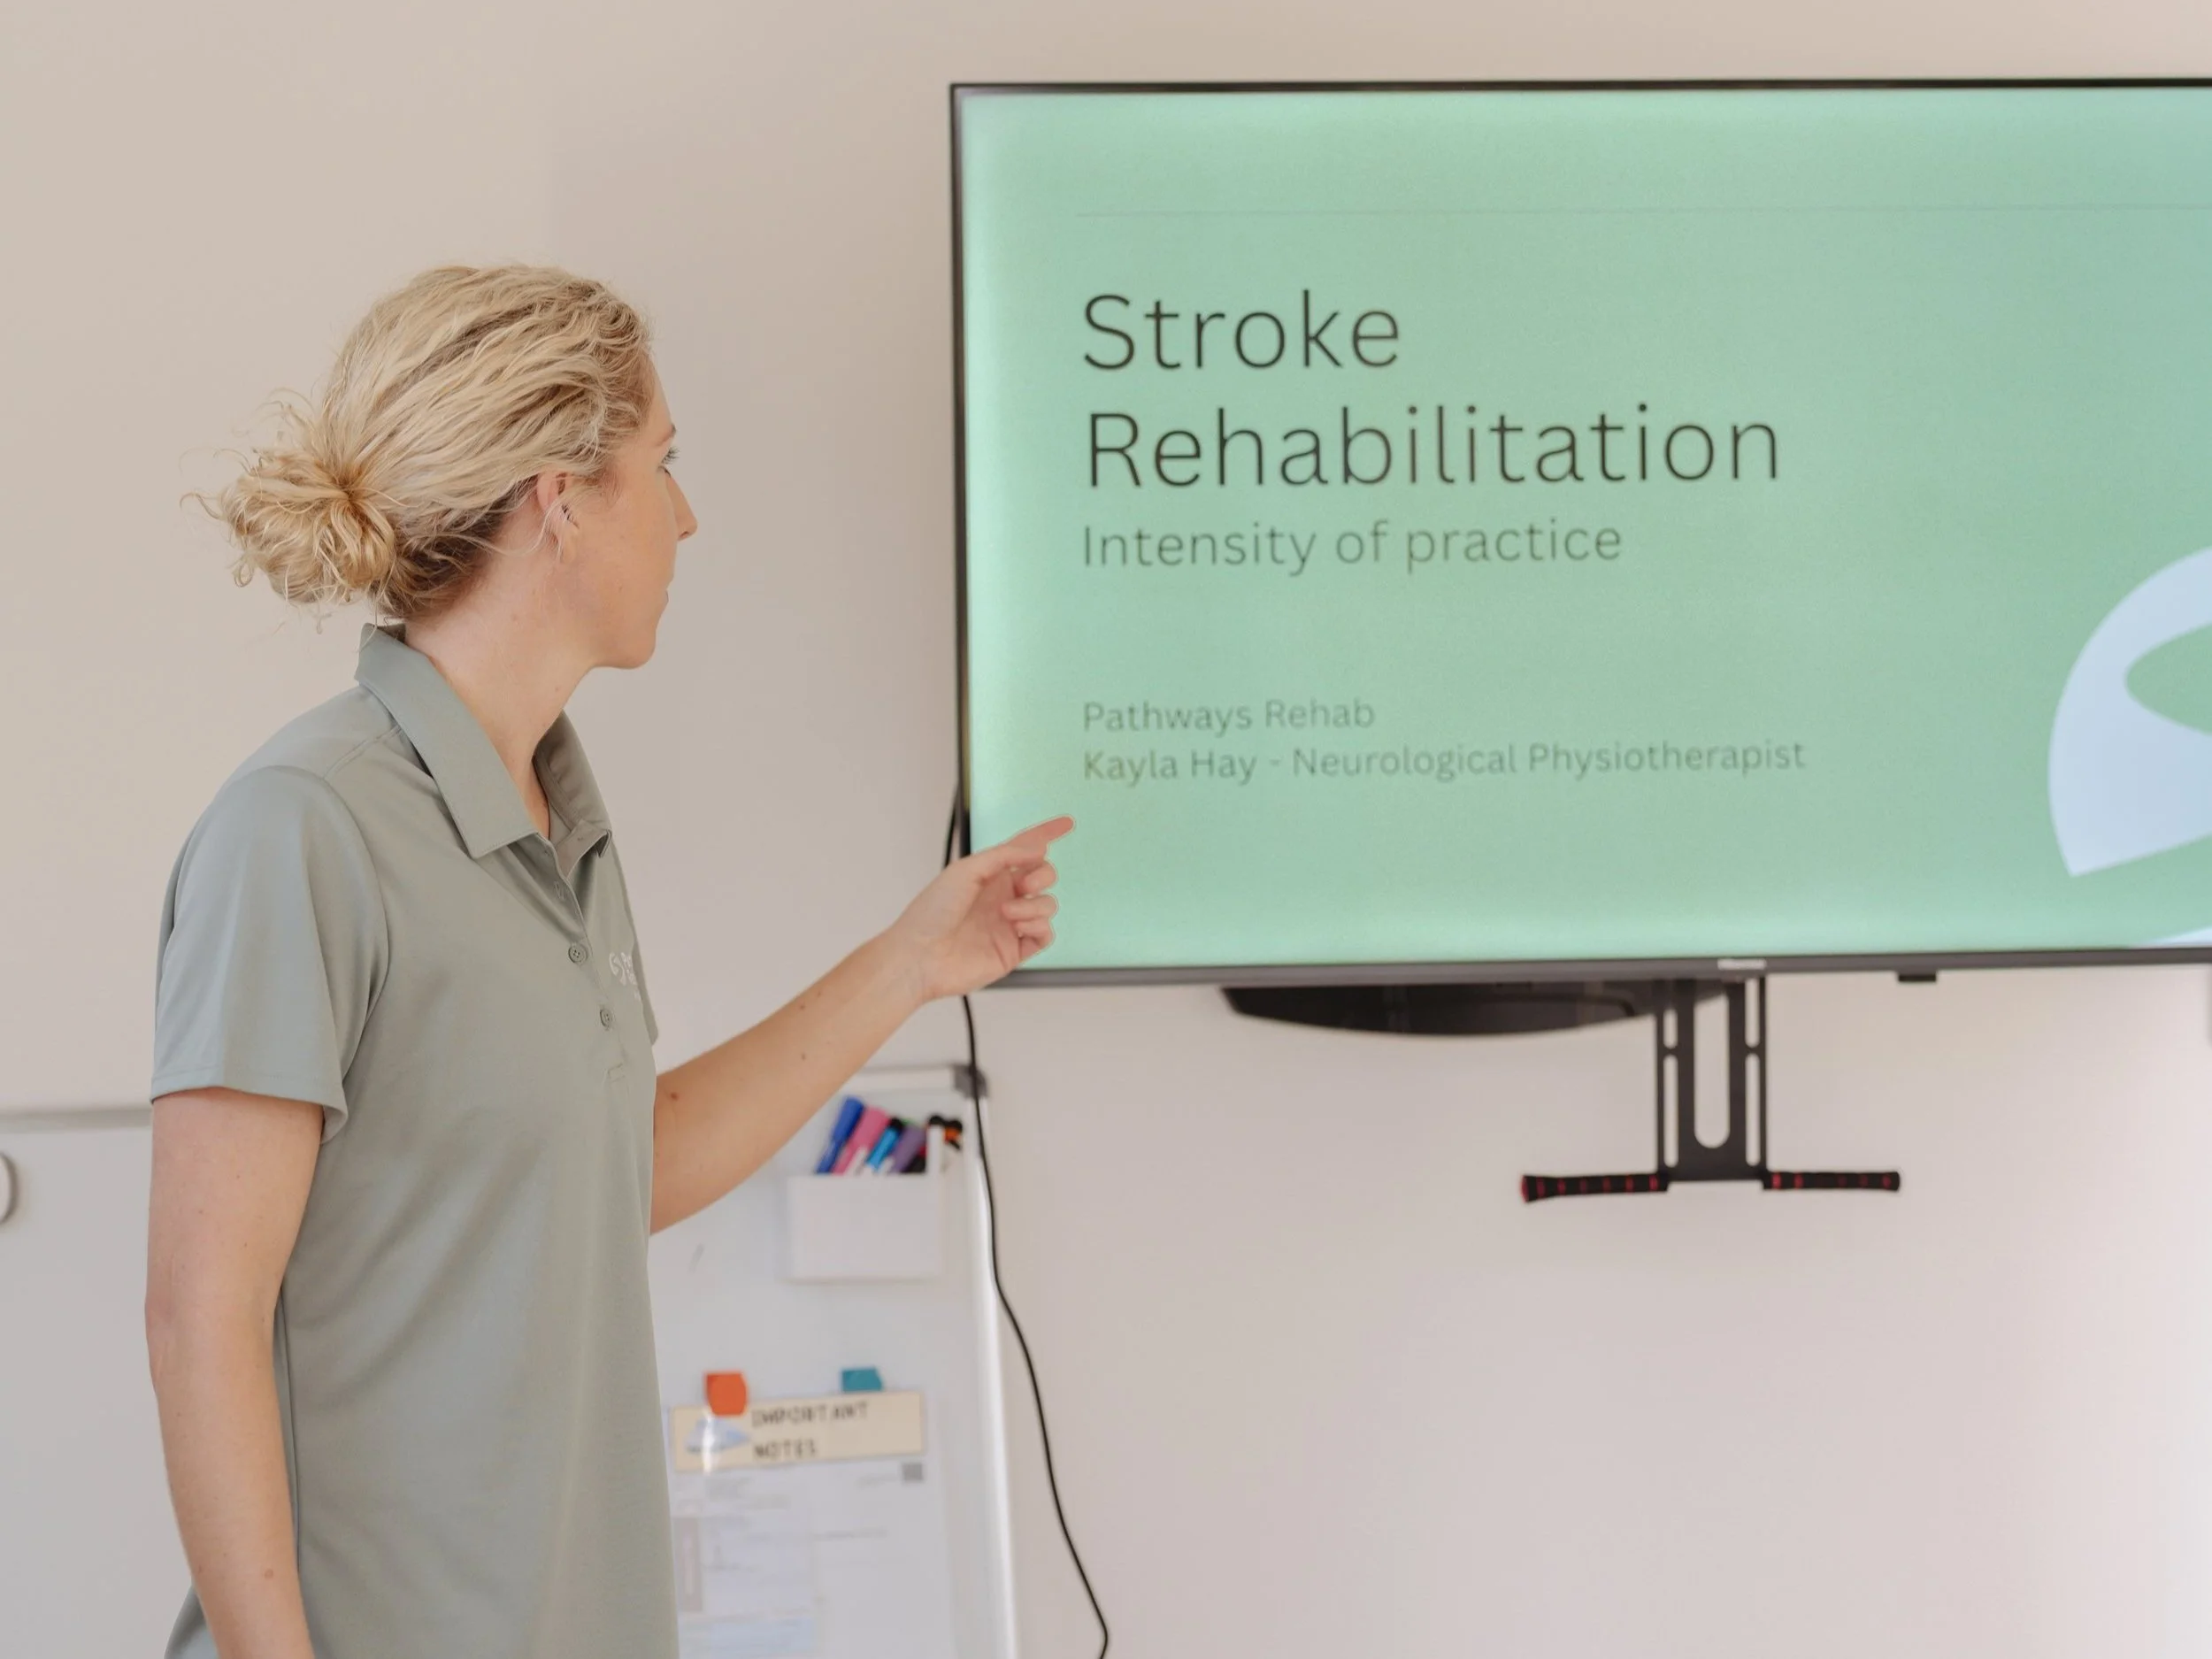

A stroke occurs when blood flow to part of the brain is interrupted, either by a blockage or rupture of a blood vessel. Depending on the brain area area affected, stroke symptoms vary and cause problems with movement, sensation, speech, swallowing, vision, thinking, behaviour and energy levels.

How can physiotherapy help ?

Physiotherapy plays a crucial role in stroke rehabilitation, supporting the brain’s ability to rewire itself; called neuroplasticity, helping restore function and maximise recovery.Our services:

Comprehensive assessment - strength, coordination, balance, muscle tone, mobility

Education - fatigue, pain, and falls prevention

Practice and relearning of daily tasks - bed mobility, standing, transfers, walking

Upper limb and hand function training

Shoulder care and device use - electrical stimulation

Spasticity management

Recommendations of equipment - gait aids, orthotics, assistive technology

Carer training to support skill practice at home

Goal setting and support for community participation

Assistance with accessing funding bodies to support your needs

Coordination with your healthcare team for holistic care - neurologist, occupation therapist, speech therapist, exercise physiologist